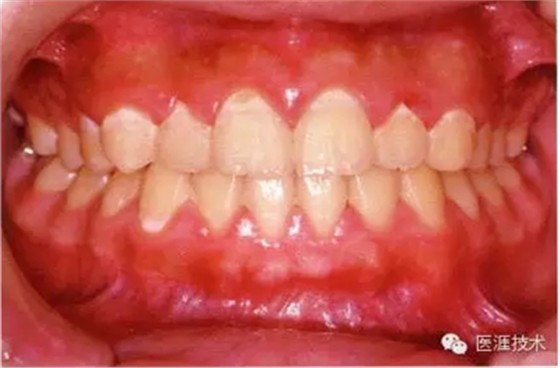

26歲男性牙齦炎的臨床圖像

26歲男性。開(kāi)口呼吸。混合有牙齦發(fā)紅、腫脹與纖維性肥厚。菌斑干燥牢牢黏住,刷牙難以刷掉。